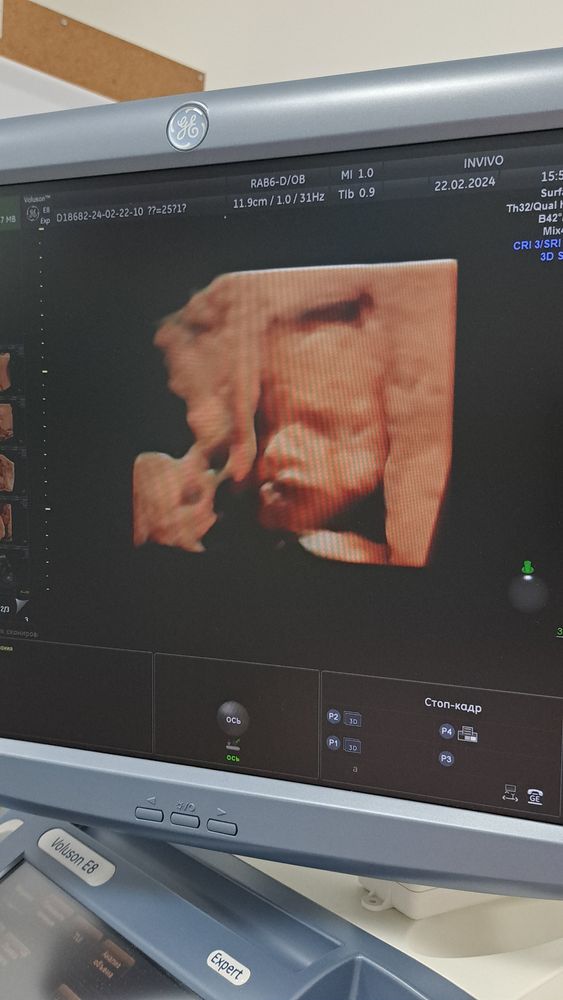

Мой 3 пупсик))))

И он так нам с мужем напомнил нашего пока младшенького🩵🩵🩵

Опять мальчик🙉 Привет декрет)))))))